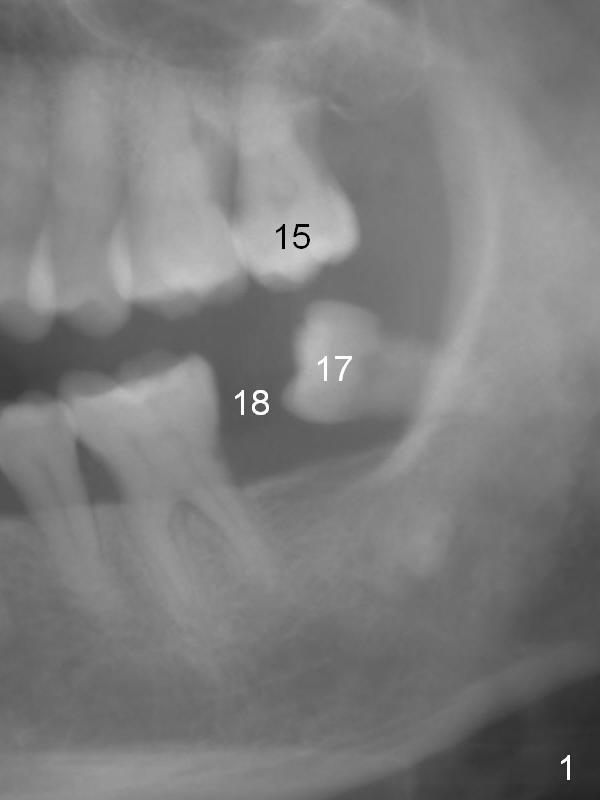

A 53-year-old lady has a small statue. The tooth #18 was extracted due to #17 impaction (Fig.1). To prevent further supraeruption of #15, an implant is to be placed at the site of #18 (Fig.2). After use of a 4 mm implant spacer and starter and 8 mm pilot drills, insert a short parallel pin for occlusion check and a calibrated one for X-ray. A relatively small and short implant will be sufficient for function. Scaling & root planing and #17 extraction have been finished.